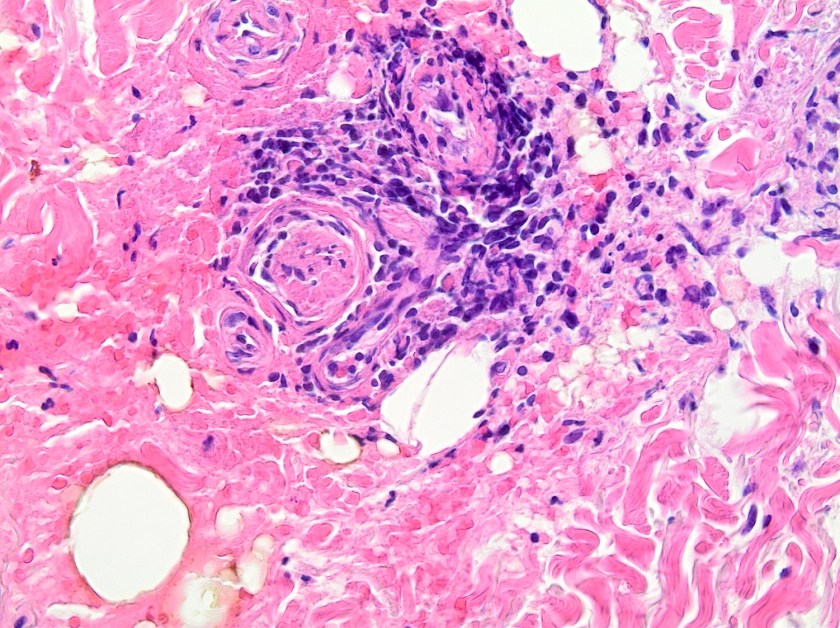

On histologic examination of the skin biopsy, nodular, superficial and deep granulomatous inflammation was noted surrounding eccrine glands and engulfing nerves (Images 1-3). Fite staining illustrated numerous acid fast bacilli (Image 4) and, given the geographic location of the patient and clinical symptoms, was felt to be highly suggestive of Mycobacterium leprae. The case was sent for confirmatory testing by polymerase chain reaction (PCR). All cultures collected were negative.

The diagnosis of M. leprae is largely a clinical one as the organism is not able to be grown on artificial media, but histology and confirmatory PCR are useful adjuncts. Skin biopsies should be full thickness and include the deep dermis. Ideally, the most active edge of the most active lesion should be biopsied. There is a spectrum of M. leprae which ranges from few lesions and a paucity of bacilli (tuberculoid leprosy) to widespread skin involvement with numerous bacilli (lepromatous leprosy). Histologically, there are granulomatous aggregates of epithelioid cells, multinucleate giant cells and lymphocytes and inflammation often engulfs sweat glands and nerves. Small lesions that have poorly defined borders and are found on the elbows, knees or ears are where bacilli tend to be located. A Fite stain is useful to highlight the acid fast bacilli located in the macrophages within the inflammatory nodules. M. leprae PCR can also be performed on blood, urine, nasal cavity specimens and skin biopsies as a sensitive diagnostic technique. PCR can also be used to detect certain genes that confer resistance to common treatment drugs such as rifampin, ofloxacin and dapsone.